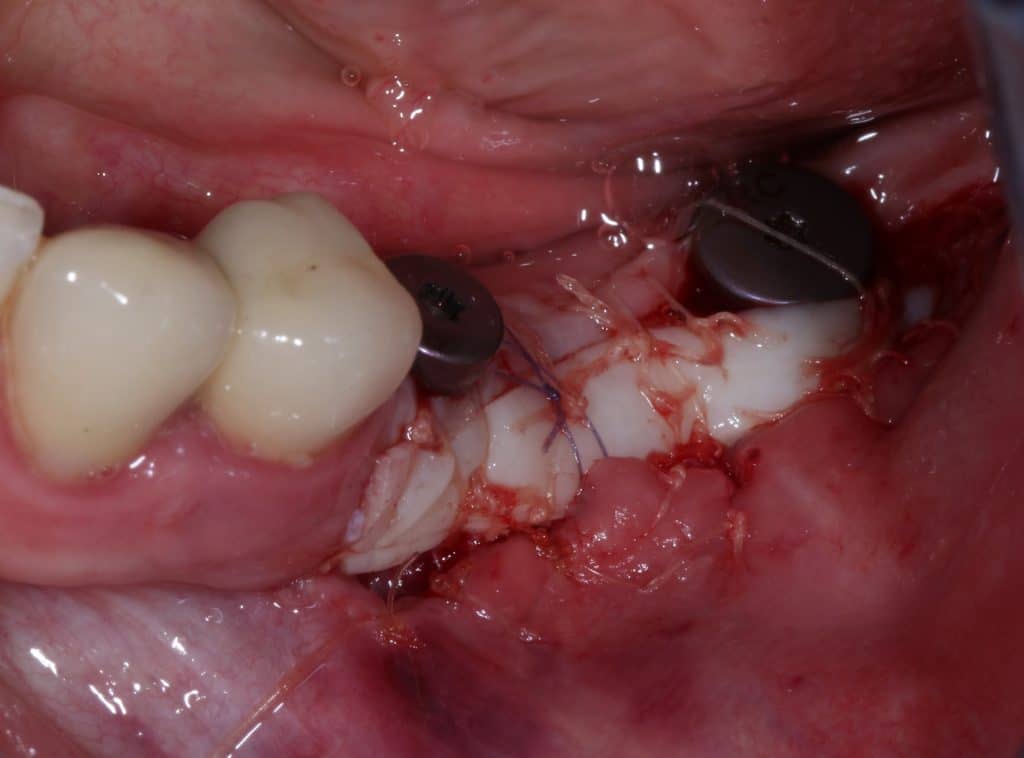

Tissue condition at the time of reopening

Implants re-opening